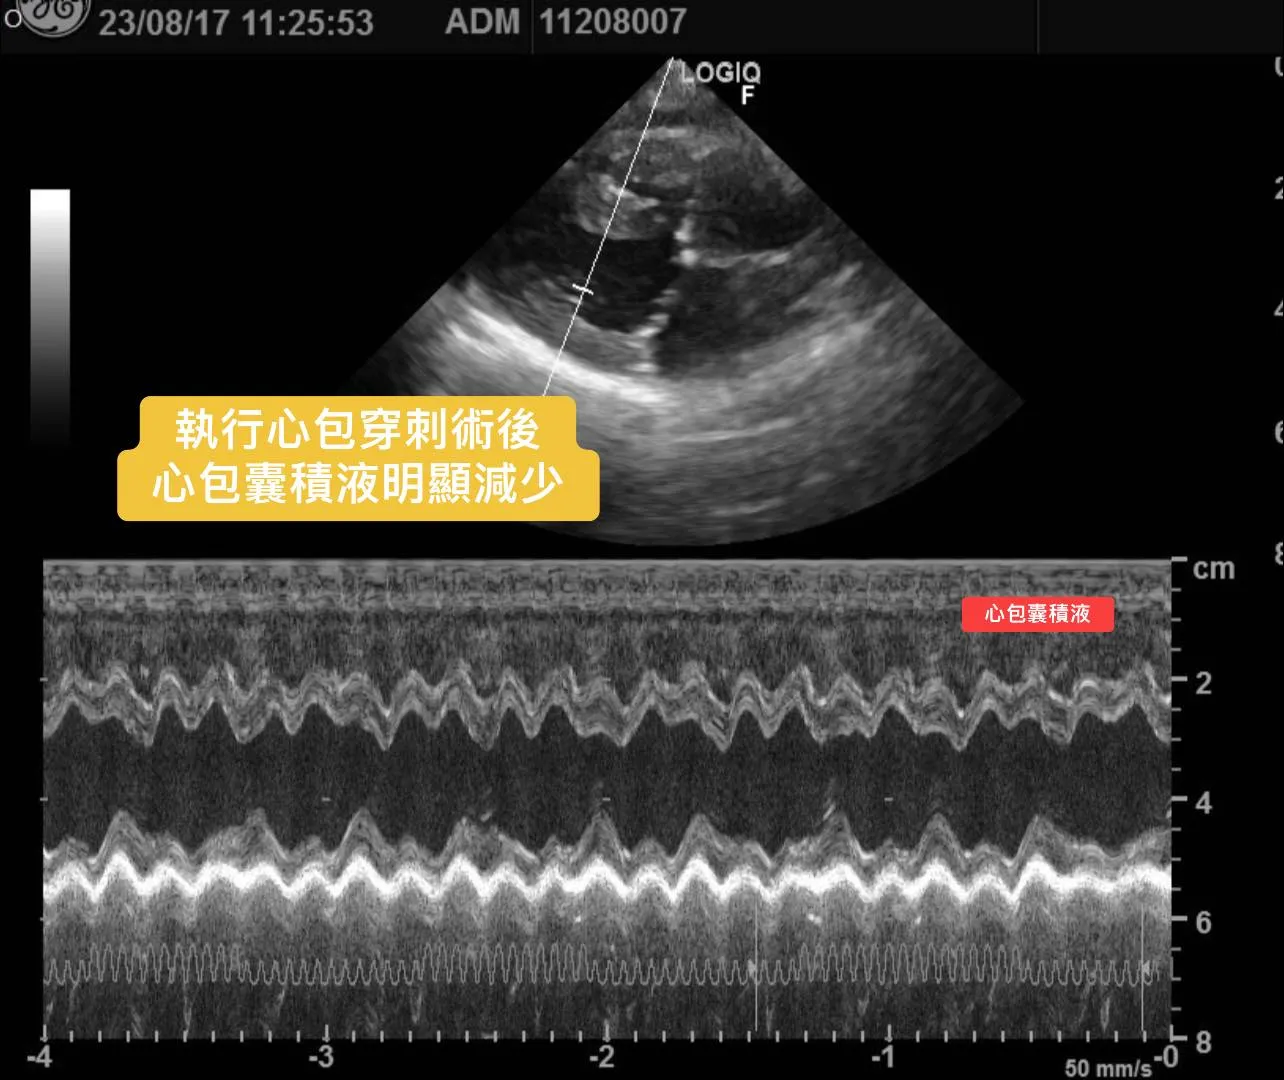

3. 心臟超音波檢查發現「大量心包囊積液」。

心包穿刺術後,毛孩立即改善喘的問題。

一週後回診時,毛孩精神食慾正常,不會喘與咳嗽,心包囊與腹水狀況也改善許多。